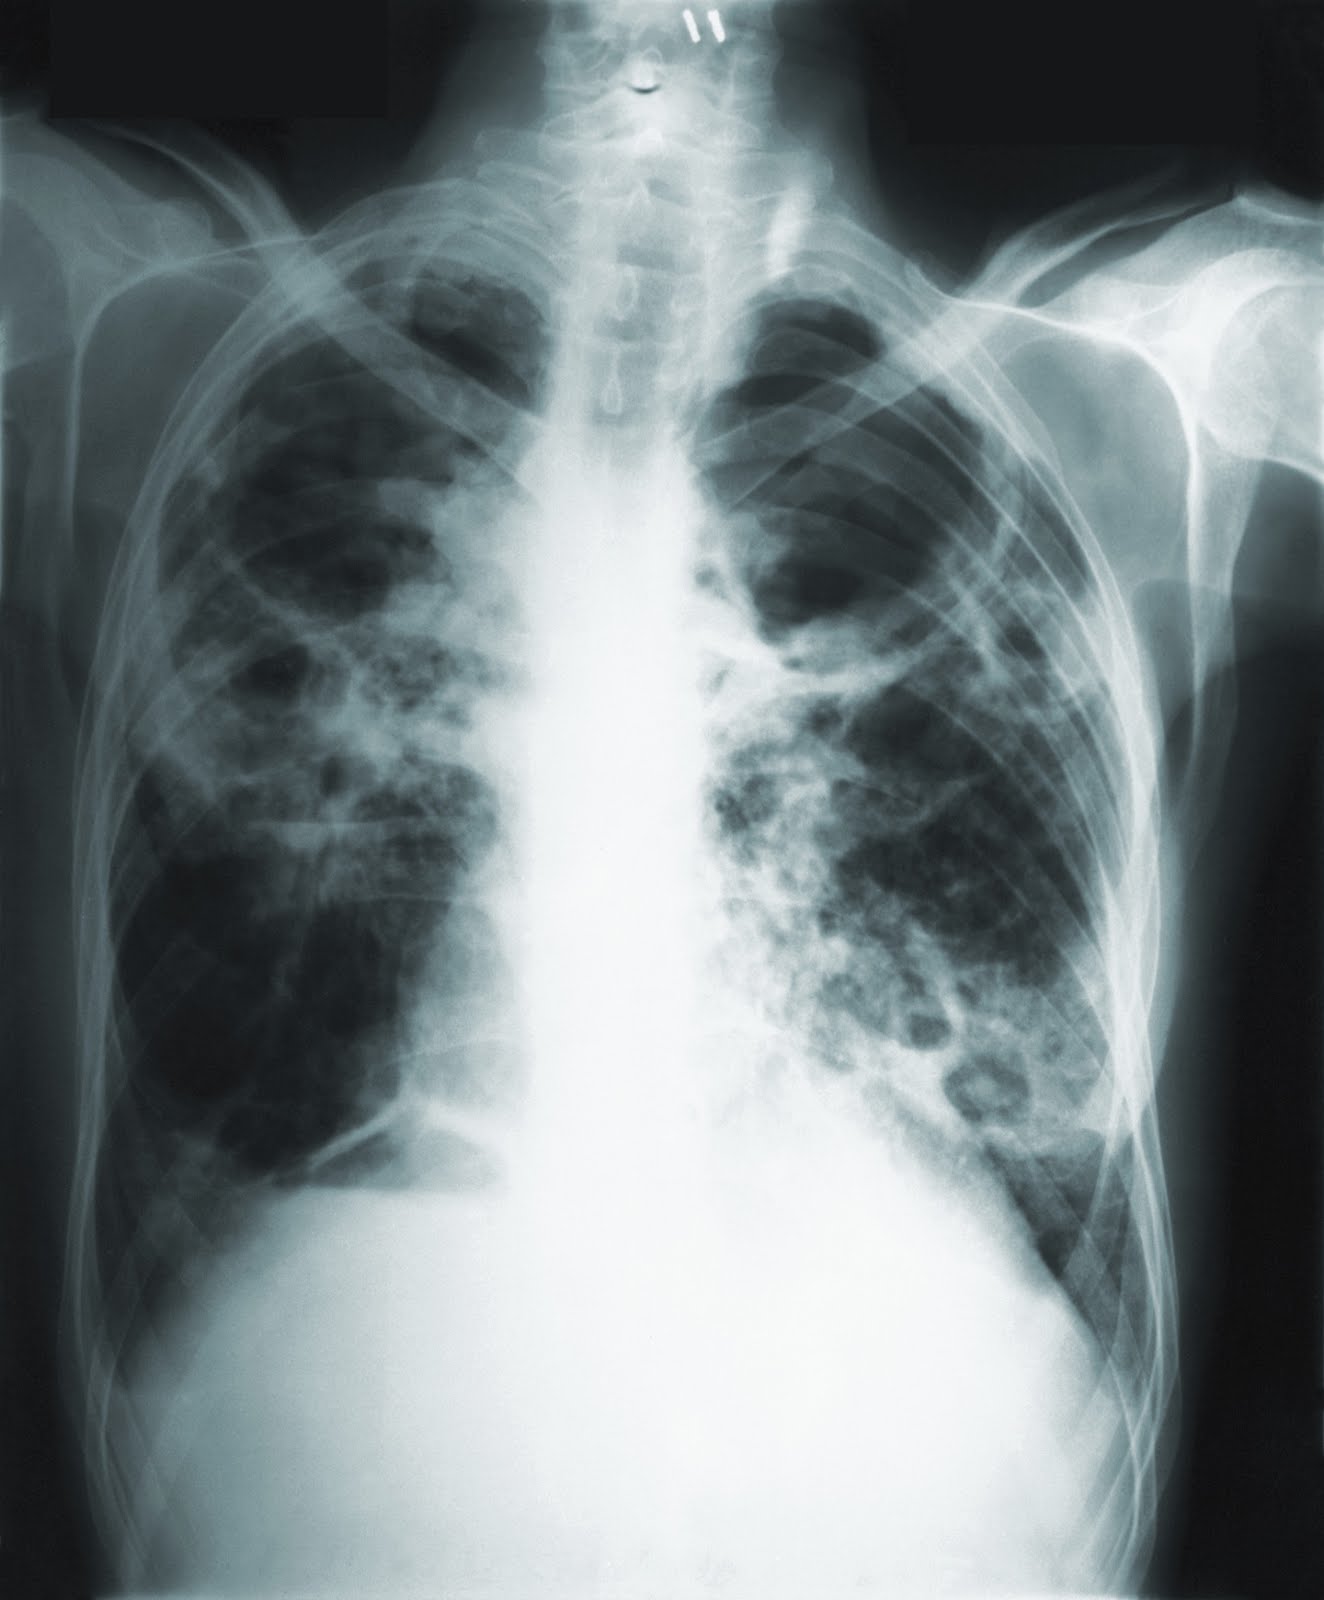

CDC via AP